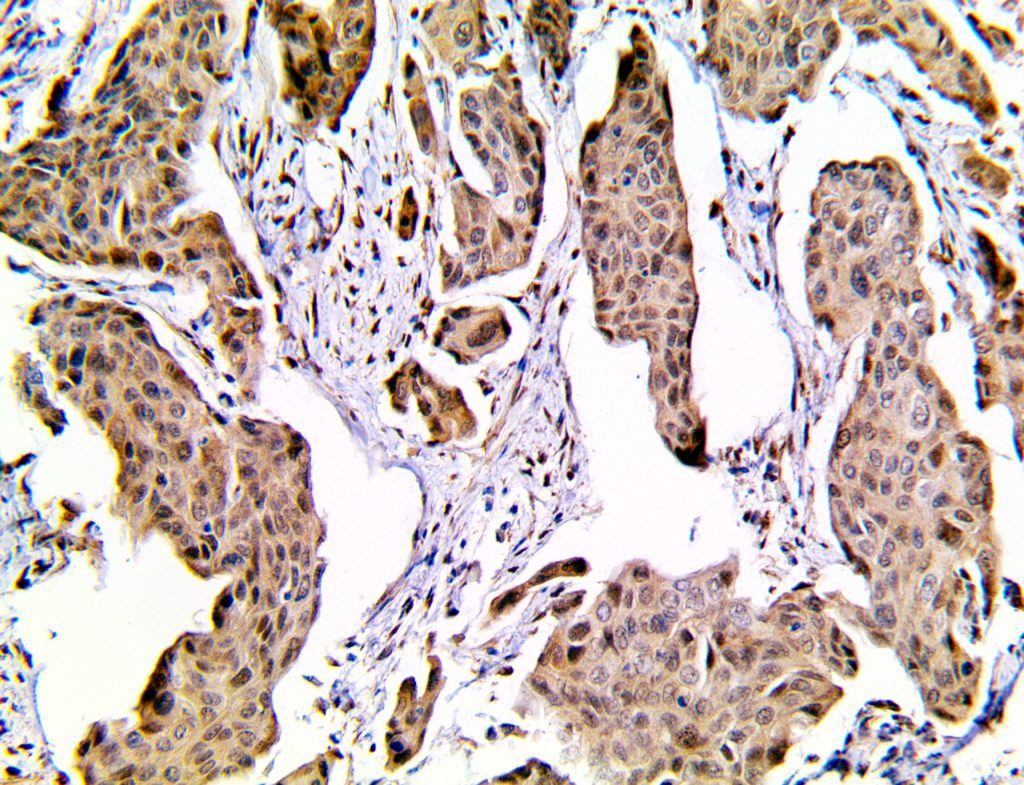

It is the ICU physician who is most likely to witness one of the deadliest manifestations of the abnormal immunological response, the cytokine storm syndrome (CSS). This response is also referred to by some as the cytokine release syndrome (CRS). CSS is characterized by continuous activation and expansion of macrophage and lymphocyte populations, which secrete large amounts of cytokines, causing the cytokine storm. This massive cytokine release is akin to hemophagocytic lymphohistiocytosis (HLH) disease, a syndrome characterized by initial unchecked and persistent activation of cytotoxic T lymphocytes and NK cells.